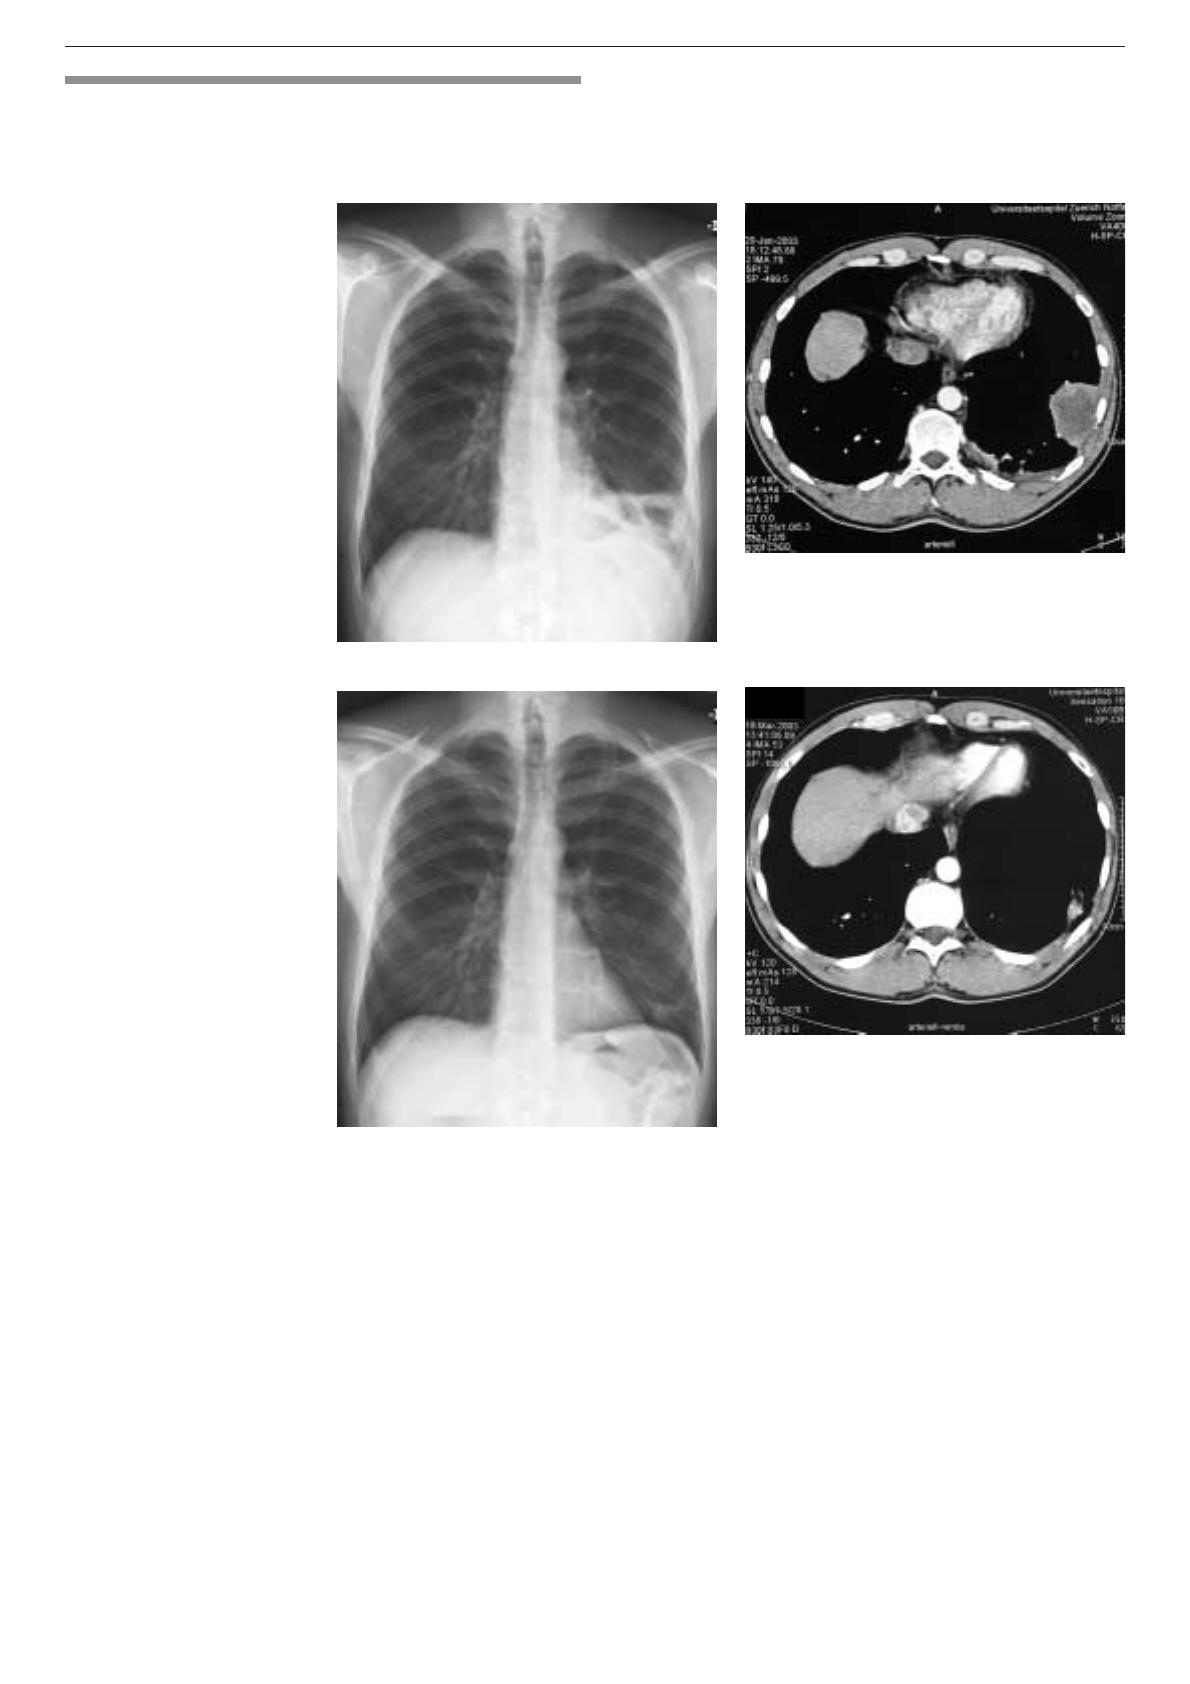

Figure 1.

Patiente de 27 ans ayant

une pneumonie lobaire bilatérale

étendue, une leucocytose à

19000/µl, une CRP à 180 mg/l et

une pneumonie à mycoplasmes

confirmée par réaction en chaîne

de polymérases.

ab

cd

Figure 3.

Patient ayant un abcès

pulmonaire à la base gauche.

Guérison pratiquement totale

après 8 semaines d’antibio-

thérapie par amoxicilline/acide

clavulanique.